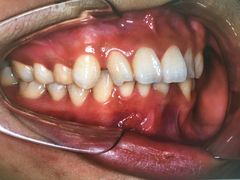

• 固瑞齿科(国贸门诊店)

• -固瑞齿科(国贸门诊店)

点小评3091610863 | 18-12-31

报错